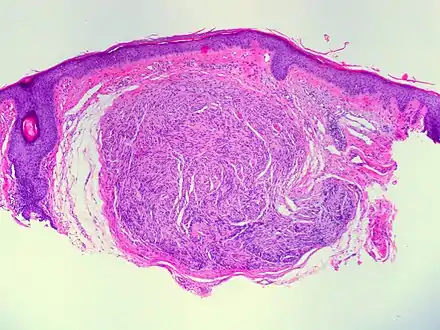

Micrograph of a palisaded encapsulated neuroma

Palisaded encapsulated neuroma (PEN) is a rare, benign cutaneous condition characterized by small, firm, non-pigmented nodules or papules.[1][2] They typically occur as a solitary (single) lesion near the mucocutaneous junction of the skin of the face, although they can occur elsewhere on the body.[3]

As mentioned previously, PEN is a benign, firm, flesh-coloured lesion that typically occurs in dermis of the skin of the face. The lesions are typically between 2–6mm and are slow-growing.[3][4]

PEN is diagnosed by clinical recognition of the lesion and on subsequent histologic examination. Typically, the lesions are suspected to be schwannomas or neurofibromas clinically with PEN being an incidental finding on histology.[3]

PEN is typically diagnosed in patients between the ages of 40 and 60 years and occurs more frequently in females than males. The diagnosis of PEN may be difficult, even with confirmatory histology, due to its histological similarities with schwannomas and neurofibromas. It is imperative that the correct diagnosis is made the misdiagnosis of a neurofibroma may lead to unnecessary further investigation into associated systemic syndromes such as neurofibromatosis type 1 or multiple endocrine neoplasia syndrome.[3][4]